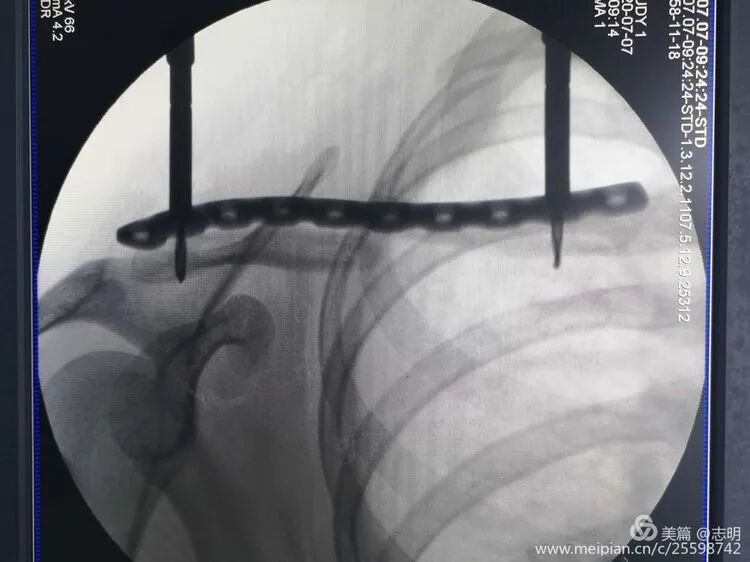

- Temporary Fixation: Once an acceptable reduction is achieved, maintain it with temporary percutaneous K-wires. As noted in the original text, "对于长斜形等易临时固定的骨折,可经皮钻入1.5mm克氏针维持复位" (For long oblique fractures and others easily temporarily fixed, 1.5mm Kirschner wires can be percutaneously drilled to maintain reduction). Ensure K-wires do not interfere with subsequent plate placement.

(Fluoroscopy showing K-wire stabilization).

- Temporary Fixation: Once a satisfactory reduction is achieved, it must be temporarily secured prior to plate application. Percutaneous Kirschner wires (K-wires) are commonly used for this purpose. The seed content states: "对于长斜形等易临时固定的骨折,可经皮钻入1.5mm克氏针维持复位" (For long oblique fractures and others easily temporarily fixed, 1.5mm Kirschner wires can be percutaneously drilled to maintain reduction). Ensure that the K-wires are placed in a manner that does not impede subsequent plate placement or screw trajectory.

(X-ray showing temporary K-wire fixation after reduction).(Fluoroscopic image demonstrating K-wire placement for temporary reduction).